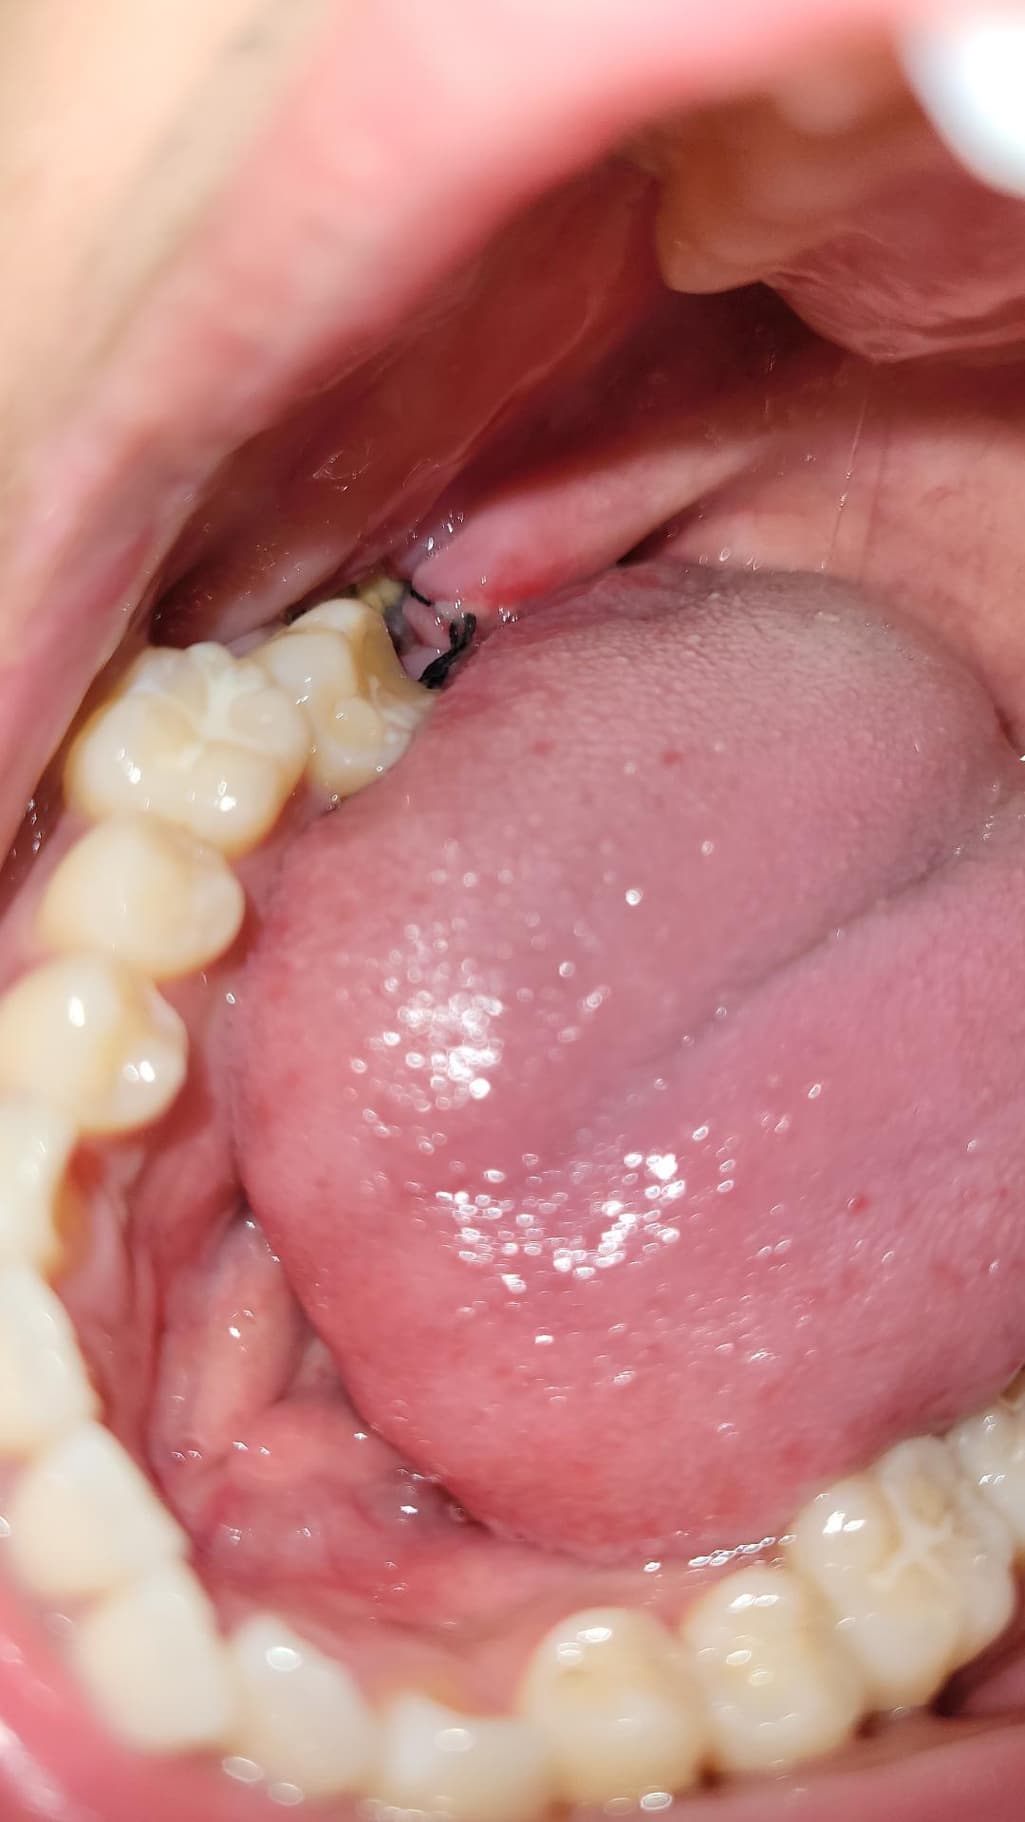

이거 혹시 드라이소켓 같은건가요?? 실밥이 풀린건가요...

이게 실밥이 풀린건지 안에 흰색이 보여서 그러는데 이게 멀까요... 아 진짜 사랑니 뽑은지는 3일 됐는데 바로 치과 가야할까요?? 아니면 어떡해야할까요

상처회복과정에서 자연스레 생기는 조직입니다. 그것들이 나중에 잇몸 살로 변하면서 아무는 것입니다. 걱정하지 않으셔도 돼고, 3일차면 거의 괜찮을테지만 혹시 모르니 떨어지거나 자극되지 않도록 주의하시고 음식물이 끼이면 물 가글로 빼주시면 좋습니다.

발치를 하고 나면 발치를 한부위가 아물면서 하얀색 가피등이 형성될수 있습니다. 문제가 되는것은 아니며 발치한 부위가 아물면서 생기는 증상입니다.

하얀색은 잇몸이 치유되는 조직으로 보이고, 실밥은 느슨해진 상태입니다. 드라이소겟은 참을수 없는 통증이 동반됩니다. 염려가 된다면 치과에 내원하여 소독을 받는것도 좋을것 같습니다. 건강하세요.

흰색 보이는 건 치유과정에서 생기는 염증,육아조직 같습니다

실밥은 밥먹다가, 양치하다가 지연스럽게 풀리기도 합니다